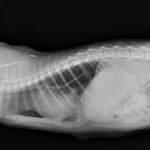

先天性心嚢横隔膜ヘルニア

若い猫が、普段はとても元気だけど、遊んだ後などに咳をする。呼吸が早くなる時がある。などの呼吸器症状で主治医を受診しました。エックス線検査の結果、心嚢横隔膜ヘルニアと診断されました。主治医より、外科的な対応のため紹介受診となりました。腹部正中切開の後、心嚢内に逸脱した、肝臓、胆嚢、小腸を腹腔内に戻し、横隔膜を再建しました。術後には、再拡張性肺水腫という病態が発生する可能性があるため、24時間体制で、患者さんを見守ります。幸い、肺水腫の傾向はみられず、5日目に無事に退院となりました。周術期には一時的に低酸素症に陥ったり、二酸化炭素濃度が上昇したりと、不安定な場面もありましたが、小さな体で本当によく頑張ってくれました。これで、普通の子猫としてどんどん大きく成長してくれると思います。本当によかった。